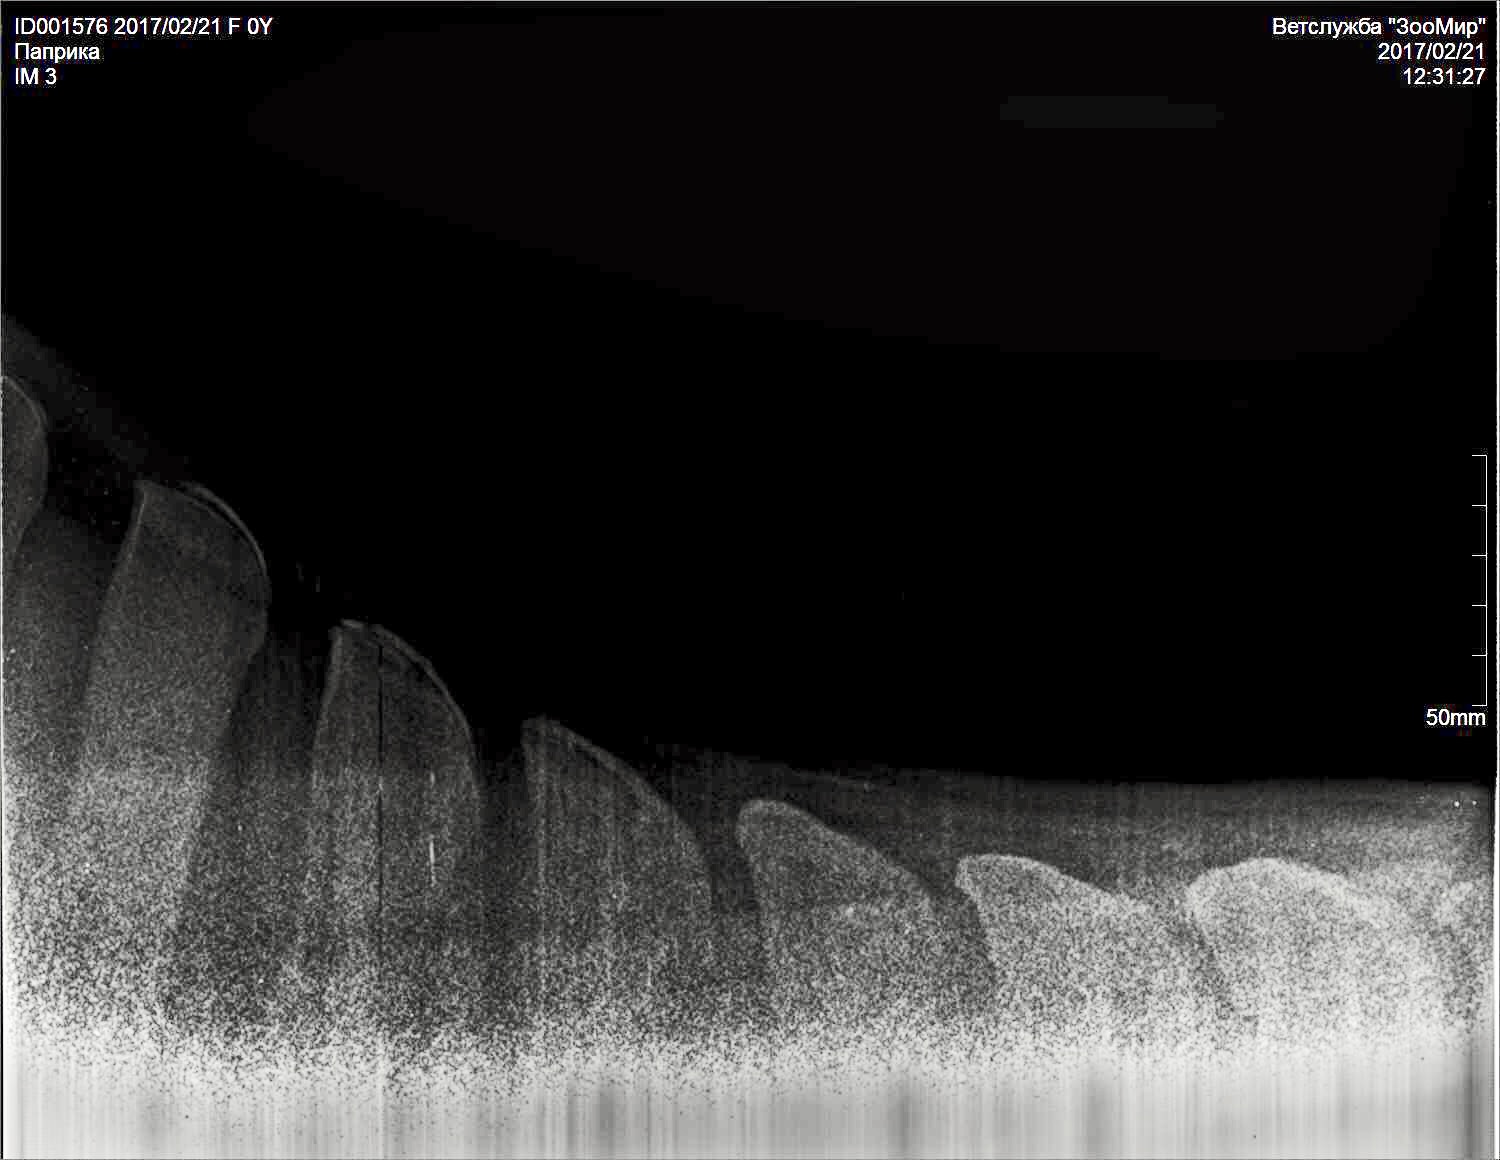

Добрый вечер!!! Помогите пожалуйста разобраться с такой ситуацией: моя лошадь стала хромать на переднюю правую ногу, лошади в мае будет 4 года, заезжена недавно. Работала 2 раза в неделю на корде, один раз верхом. Выгул ежедневный сено вдоволь, овёс пол ковша. Меня это забеспокоило и я вызвала рентген. Врач по снимкам мне сказал, что у нас киста в ПЛ ноге в челночной кости и синдром целующихся позвонков. Из лечения сказал ковать на круглые подковы, 5 фильц, поднимать пятку (лошадь не ковалась). Если подкованная будет хромать, колоть Бонефос. Лошадь молодая и с характером, блокады сделать было невозможно, выдирает ноги. Рентгенили тоже под седацией, но ноги все равно выдирала. Другой врач сказала что у нас перелом мякишного хряща, кисту не наблюдает. Я в панике! ((( Пожалуйста посмотрите снимки, все ли так серьезно?